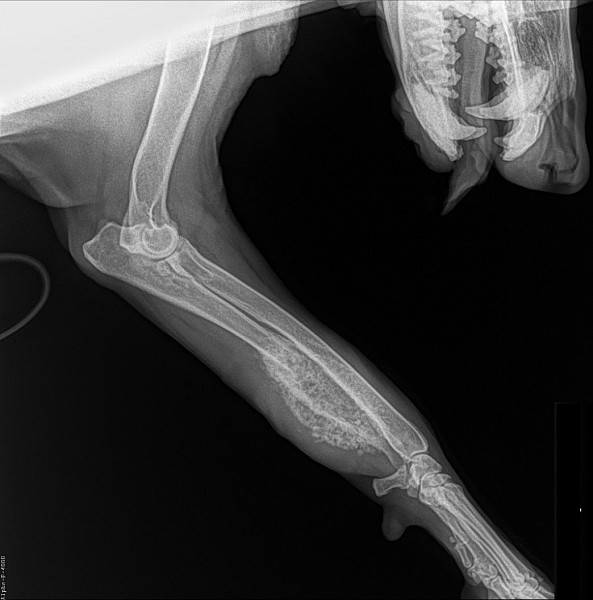

Рентген Задней Лапы Кошки: Нормы и Диагностика